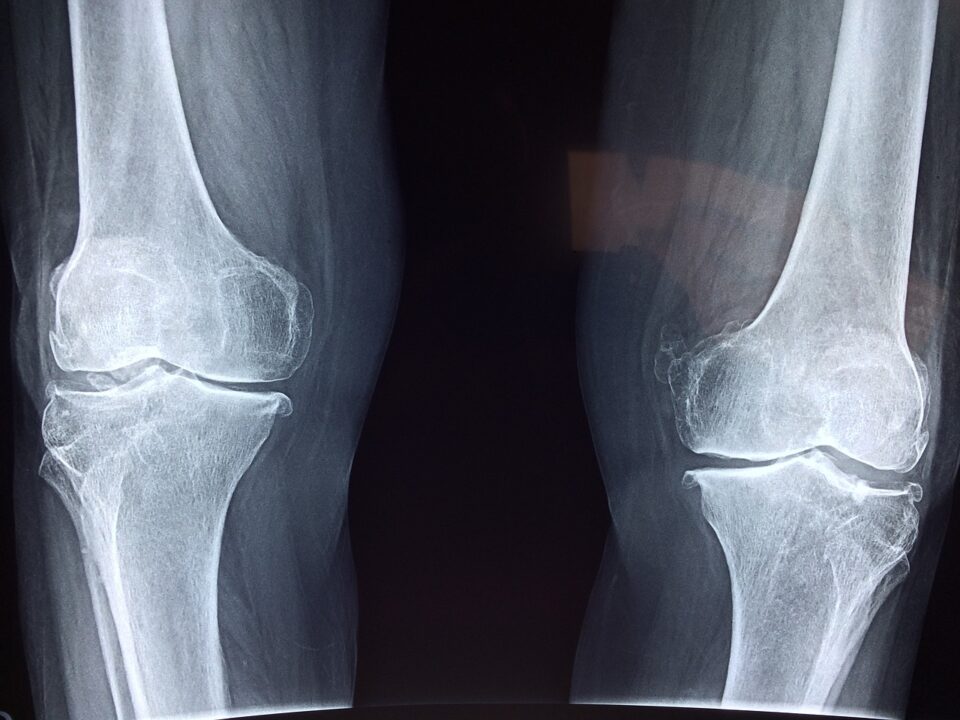

Glukozamin, eklem ağrısını tedavi etmek veya önlemek için düzenli olarak kullanılan bir takviyedir. Glukozamin, kıkırdak gelişimini desteklemede rol oynar. Kıkırdak, kemiklerinizin uçlarını kaplayan ve eklemlerinizi oluşturmaya yardımcı olan bir tür düz beyaz dokudur. Eklem sıvısı ile birlikte kıkırdak, kemiklerinizin serbestçe ve acısız hareket etmesini sağlar. Glukozaminin etkileri ve diğer faydaları ise şöyle sıralanabilir:

- Teorik olarak, glukozamin eklemlerin kayganlaşmasına ve kıkırdağın daha fazla darbe emici hale gelmesine olanak tanır. Bu da, eklem ağrısını azaltmaya yardımcı olur. Kısaca glukozamin biraz ağrıyı hafifletebilir ve diz fonksiyonunu iyileştirebilir. (1)

- Glukozamin, vücudun tüm dokularında bulunan endojen bir madde olduğundan kıkırdağın yapı malzemesidir. Bu nedenle kireçlenme gibi kıkırdak problemleri için bir önlem olarak tercih edilir. (2)

- Vücudun kendisi glukozamin üretebilir, ancak bazen vücudumuzun glukozamin takviyeleri konusunda bir yardıma ihtiyacı vardır. Vücut yaşlandıkça glukozamin üretimi azalır. Glukozamin bu nedenle esas olarak osteoartrit gibi yaşa bağlı şikayetlerle mücadele etmek için kullanılır.(2)

- Glukozamin takviyeleri, osteoartrit semptomlarının temel nedenini ele alarak kıkırdağı güçlendirmeye yardımcı olur. (3)